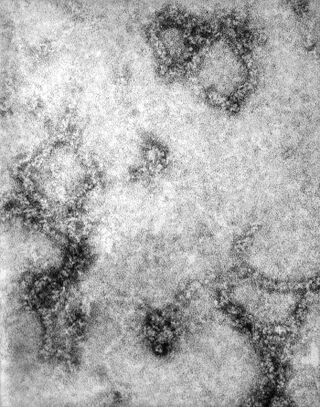

• Bottom:TEM image revealed the presence of La Crosse encephalitis virus ribonucleoprotein particles, LAC virus is a member of the Bunyaviridae virus family, California serogroup(source:CDC)